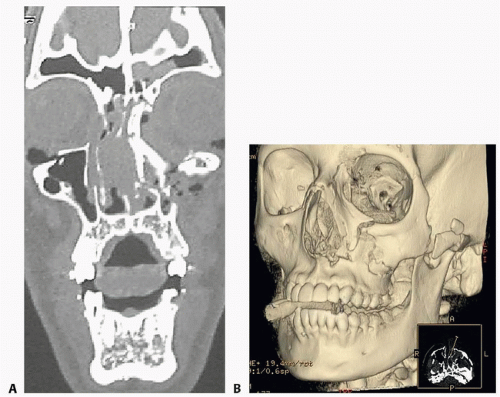

Computed tomography (CT) max-face is the diagnostic study of choice to evaluate the characteristics of fracture patterns. Considerable information can be obtained from CT imaging.

Manson’s classification according to degree of displacement/comminution is useful based on CT3:

Minimal displacement, no comminution

Moderate displacement, mild comminution

Severe displacement, major buttresses comminuted in multiple locations

Three dimensional (3D) reconstruction offers interpretation of complex fractures (FIG 4).